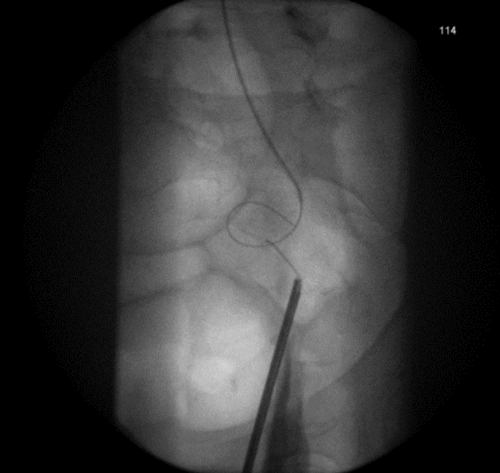

3a. Right antegrade wire insertion and pull-through.

3b. Right JJ stent in situ. Failed left antegrade wire passage.

3c. Left intraoperative nephrostogram showing obliterated left distal ureter.

3d. Right nephrostogram one week postoperative.

Figure 3: A 51-year-old woman, initially presenting with acute kidney injury, with bilateral distal ureteric obstruction secondary to locally advanced cervical cancer. Bilateral rendezvous, technically successful on right but failed on left secondary to ureterovaginal fistula.